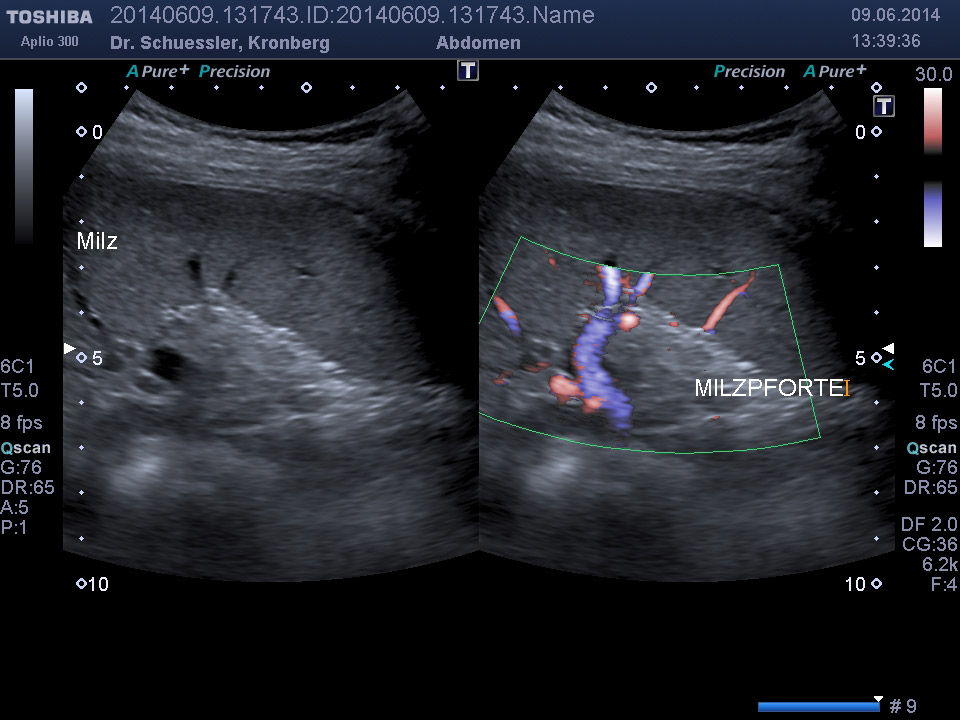

Durch Ergänzung des farbkodierten Duplexverfahrens läßt sich die Durchblutungssituation der Bauchorgane erfassen.